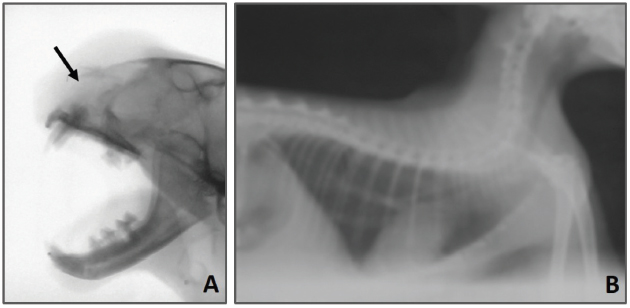

The radiographic examination of the skull revealed that there was bone lysis involving the nasal bone with no evidence of bony proliferation (see Fig. 2A). In addition, the thorax radiograph showed no signs of tumor metastasis to the lung (see Fig. 2B).

Fig. 2. (A) Lateral radiographic view of the skull showing an osteolysis involving the nasal bone (arrow). (B) Lateral radiographic view of thorax revealing the absence of evidence of metastasis.

OSA is radiographically characterized by bony proliferation, lysis, or both (Thrall, 2017). In the current case, OSA was osteolytic with no radiographic evidence of bone proliferation. In addition, no radiographic evidence of tumor metastasis to the lung was identified.